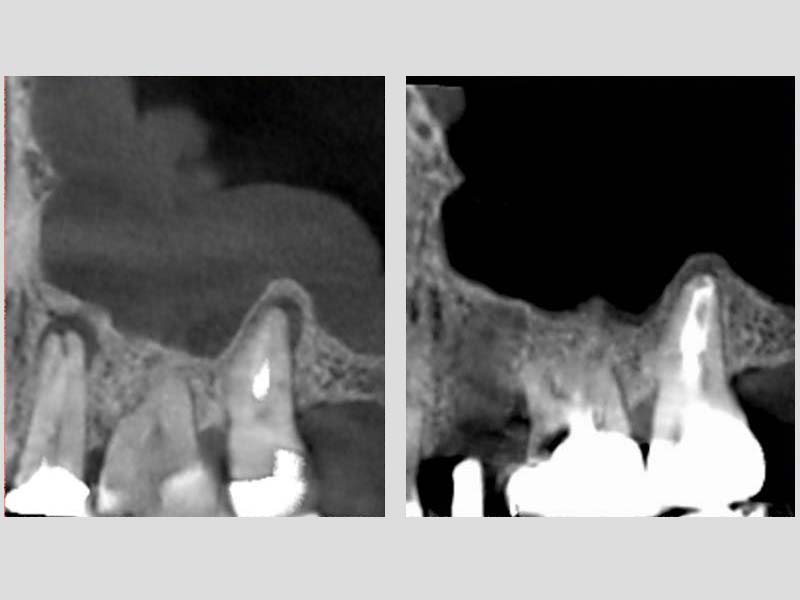

圖例為案例分享:

粉:感染增生的鼻竇黏膜

綠:原本的鼻竇範圍

紫:牙齒跟監感染,進入鼻竇

術前的電腦斷層

術後的電腦斷層,比竇黏膜已完全復原

術前 / 術後